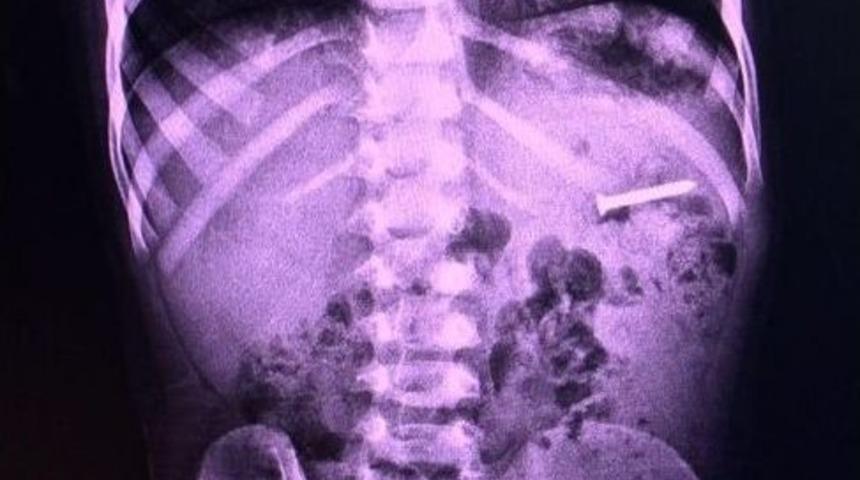

Bilecik’te 2,5 santimetre uzunluğunda vida yutan küçük çocuk, vidayı doktor kontrollünde doğal yolla çıkardı.Alınan bilgilere göre, Kurban Bayramı’nın ilk günü evde oynarken Bilecik’te 2,5 santimetre uzunluğunda vida yutan 3 yaşındaki Bahadır Selöz, yuttuğu vidayı doktor kontrollünde 2 gün sonra doğal yolla çıkardı. Babası Eğitim Bir-Sen Bilecik Şube başkanı Ahmet Selöz olan minik Bahadır, bütün aileyi korkuttu. Doktor kontrollünde yapılan çalışmalar sonrası doğal yollarla vücudundan çıkartılan vida sonrası derinden bir nefes alan baba Selöz, sosyal medya üzerinden, “ Bayramın son günü bayram ettiren Rabbime ham dolsun. İlk gün 3 yaşındaki oğlumuzun yuttuğu 2,5 cm’lik vidadan doktor kontrolünde bugün doğal yollardan kurtulduk. Dualarıyla bize destek olan bütün dostlara akrabalara teşekkürler Allah razı olsun” dedi.